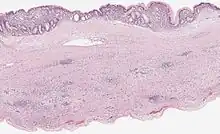

Mucinous cystadenoma of the pancreas